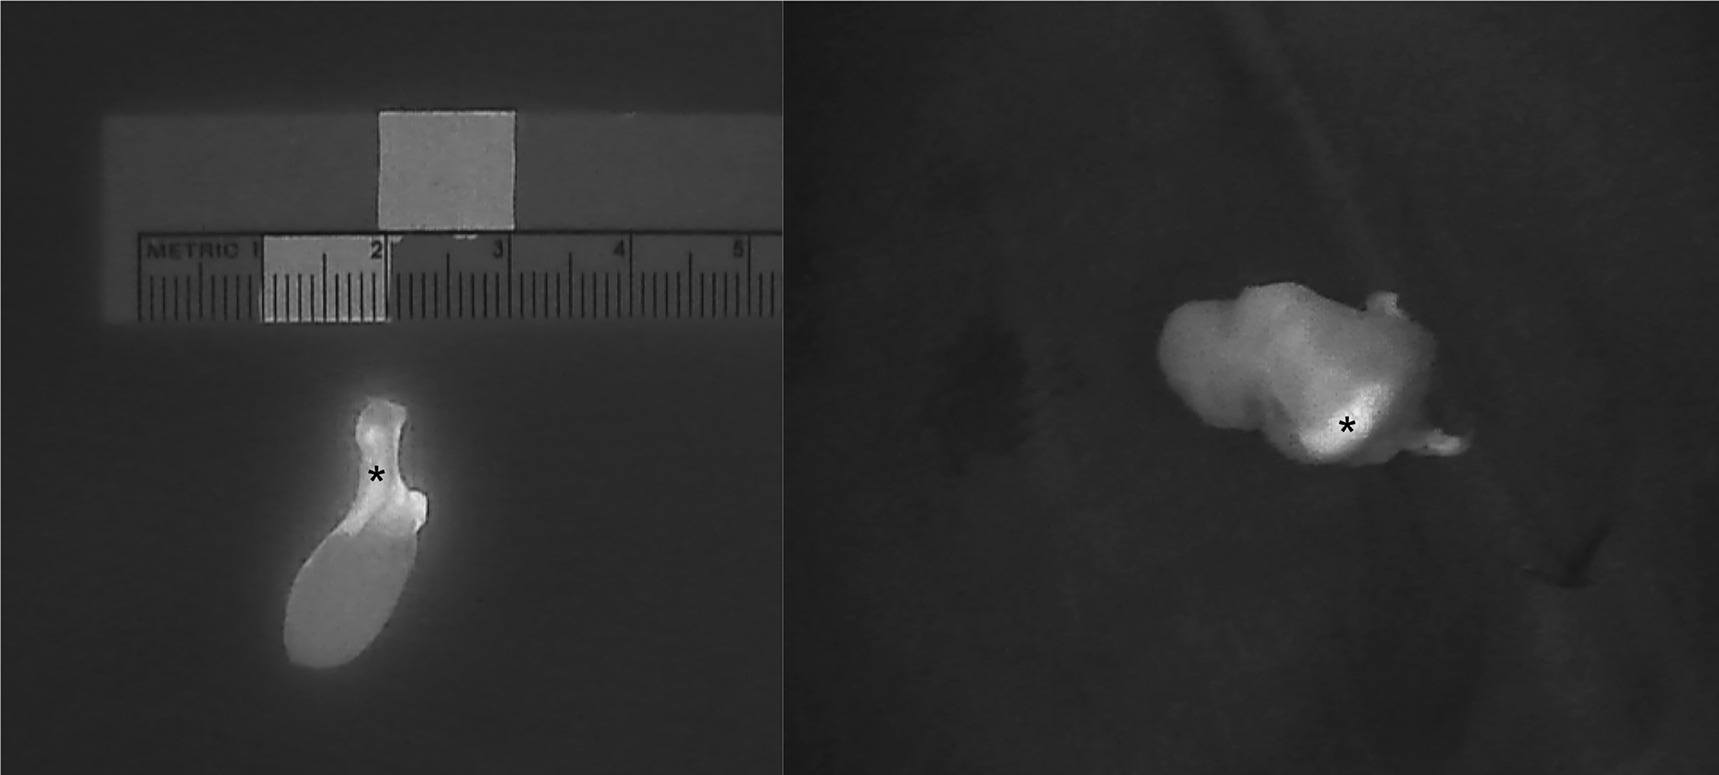

The introduction of NIRAF has vastly improved intraoperative imaging [47, 48]. Many recent studies (Table 2) have demonstrated that the use of NIRAF during thyroid surgery can improve surgical outcomes by facilitating PG identification (Figures 1 –3), which reduces the incidence of postoperative hypoparathyroidism. In particular, Benmilloud et al. showed that NIRAF improved PG identification and helped to reduce the rate of temporary postoperative hypocalcemia, parathyroid autotransplantation, and inadvertent parathyroid resection [48, 66]. In the literature, NIR devices have been shown to facilitate parathyroid gland identification by detecting their AF before conventional, visual recognition by the surgeon, in 37–67% of cases [49]. Additionally, these devices enable the early identification of PGs before surgical dissection, helping to preserve their vasculature [50]. A systematic review and meta-analysis by Barbieri et al. found that NIR fluorescence imaging reduced short and medium-term hypocalcemia compared to conventional surgery [51]. Moreover, NIRAF can detect subcapsular/intrathyroidal PGs or PGs that have been accidentally removed, which can then be resected from the thyroid specimen and auto planted back into the patient (Figures 4 and 5). In addition to the identification of normal PGs, NIRAF can help to identify a pathological PG. Parathyroid adenomas exhibit a more heterogeneous and less intense autofluorescence signature than that of normal PGs (Figure 6), enabling the differentiation between a normally functioning and a pathological PG [52, 53]. Furthermore, the fluorophore is resistant to freezing, heating, and fixing with formalin, meaning that the autofluorescence properties are preserved after gland resection [4, 29, 42, 43].

Intraoperative near-infrared autofluorescence (NIRAF) images of parathyroid adenomas after resection, demonstrating the heterogeneous and less intense fluorescence pattern that differentiates diseased parathyroid glands (PGs) from normal PGs (indicated with *). Frequently, the most intense NIRAF signal comes from residual normal parathyroid tissue in the adenoma.